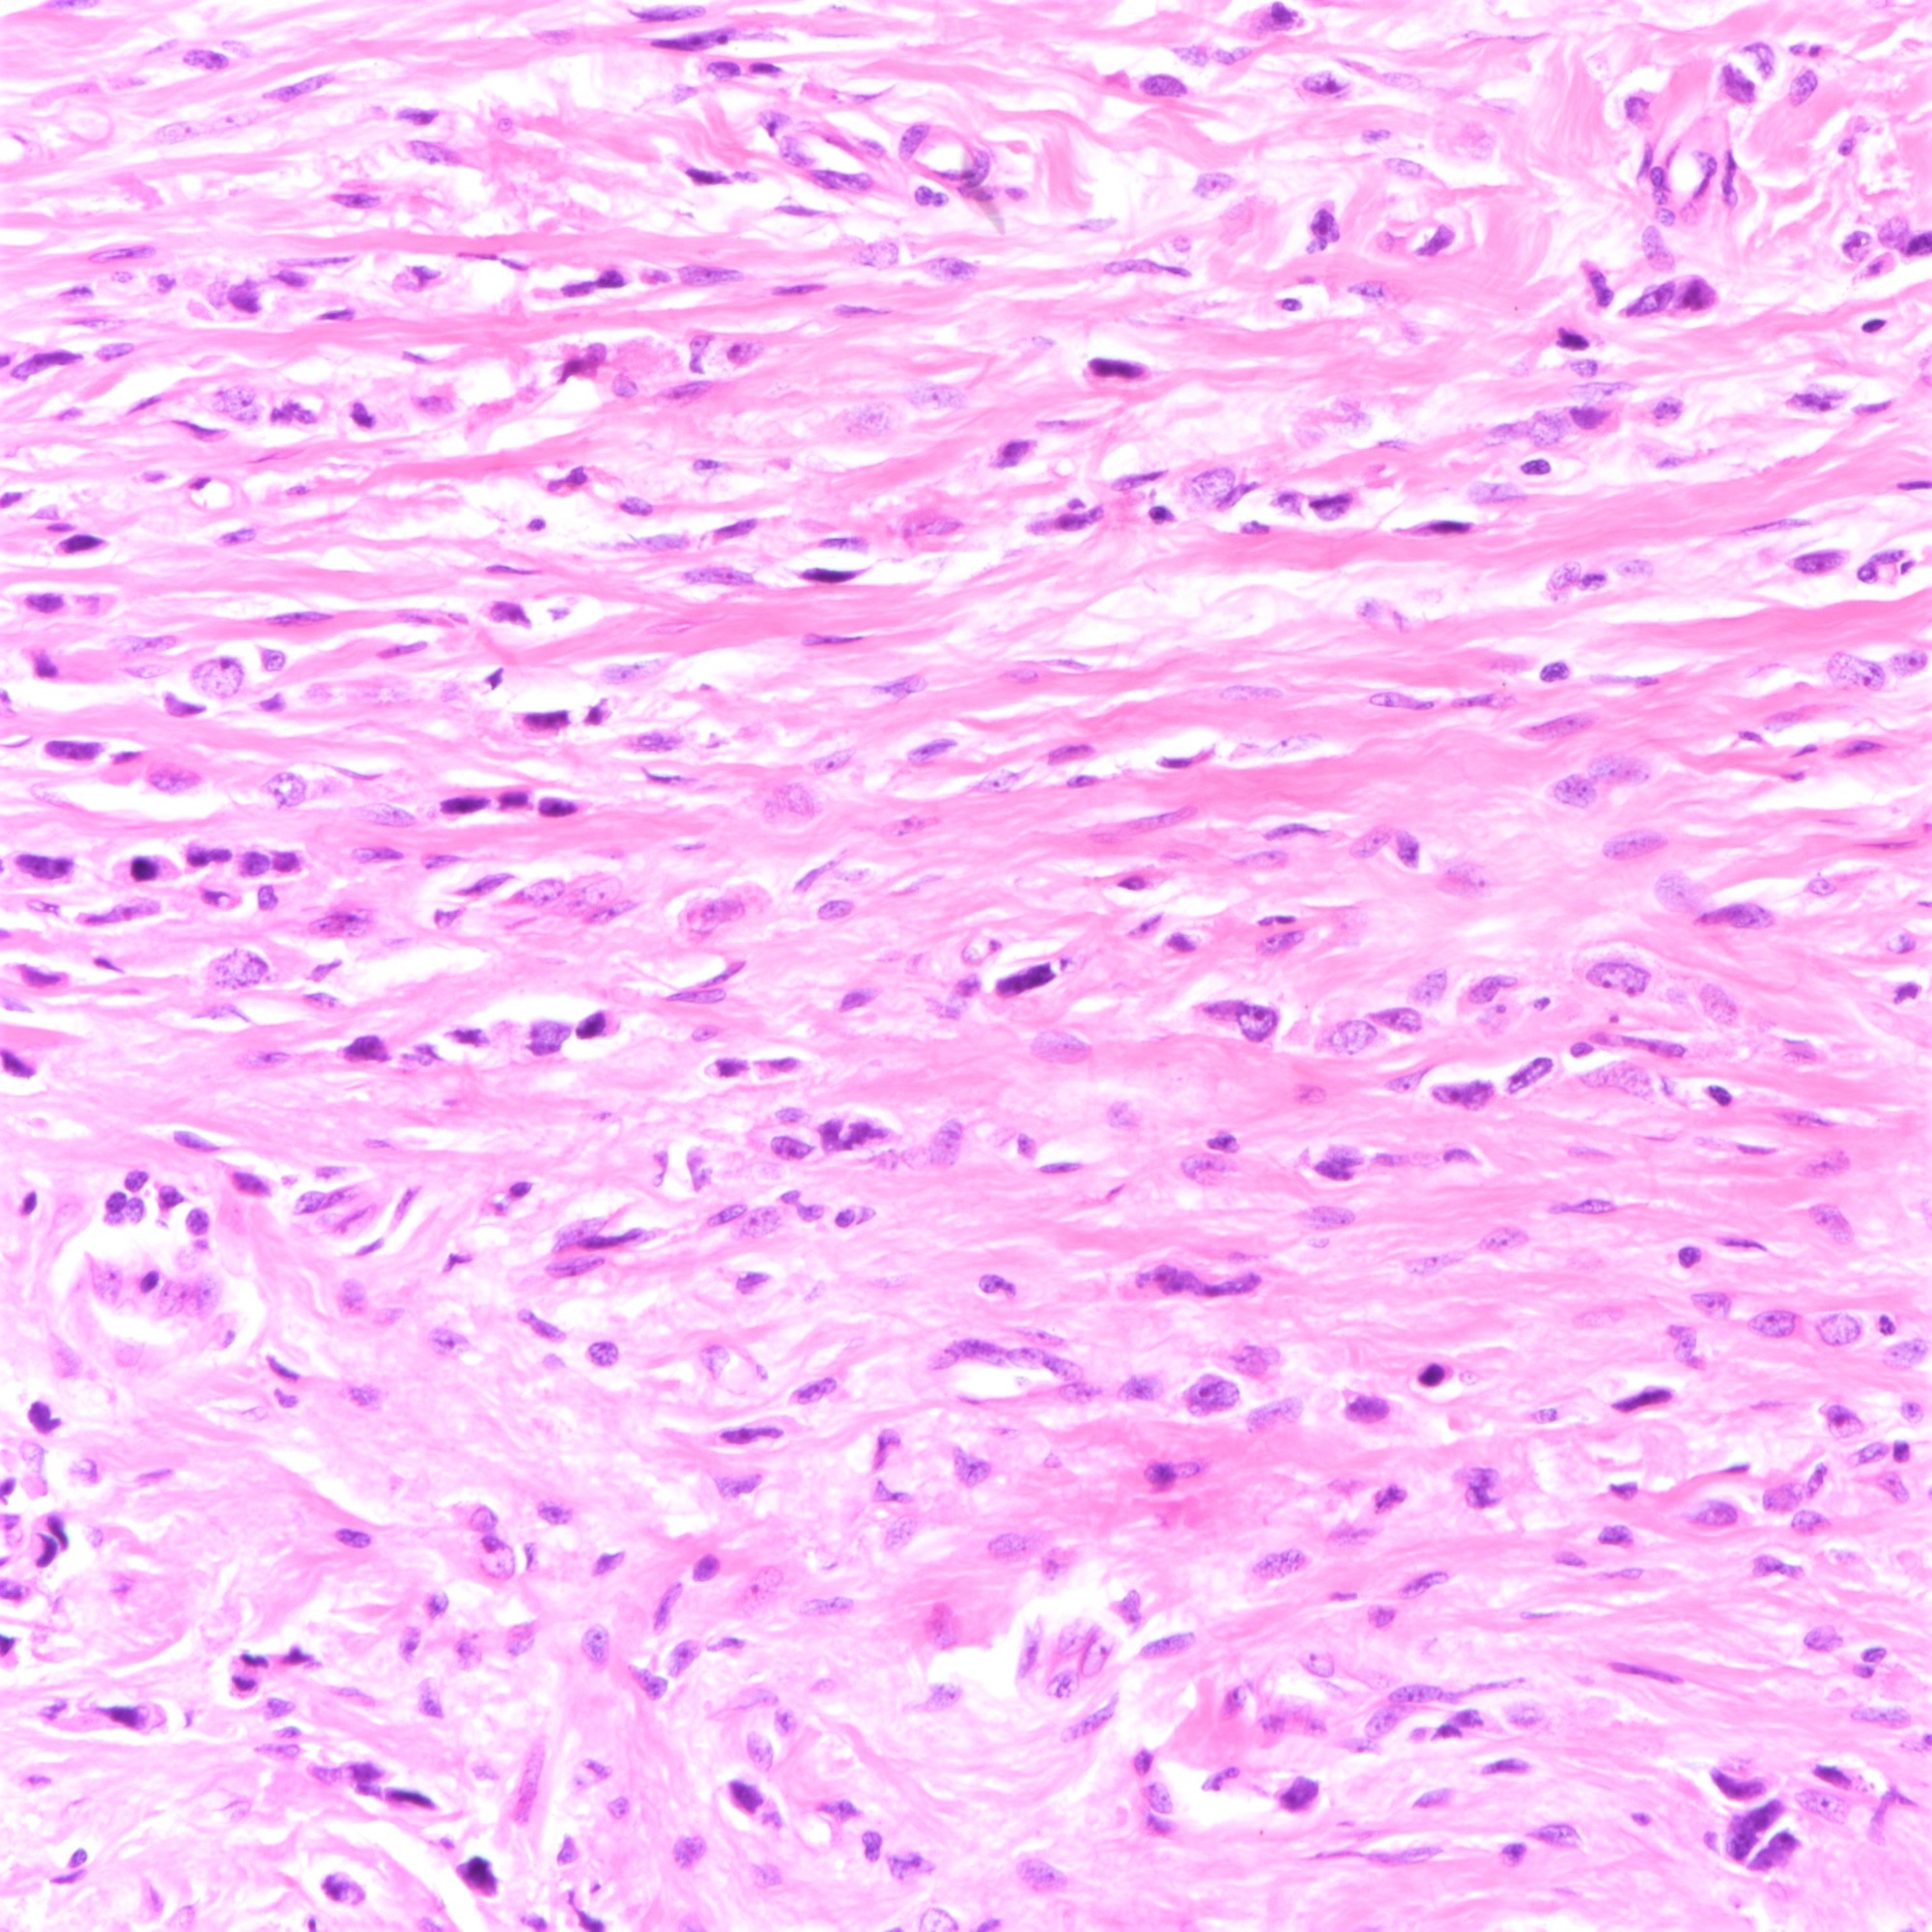

Microscopic (histologic) description

- Tumor cells arranged in single files, cords and single cells (Breast Cancer Res 2015;17:12)

- Tumor cells discohesive, small, monomorphic and lacking marked atypia

- Round or notched ovoid nuclei, usually grade 1 or 2 nuclear score

- Scant cytoplasm, occasional with intracytoplasmic lumen

- Mitosis infrequent

- Desmoplastic reaction and necrosis uncommon

Microscopic (histologic) images